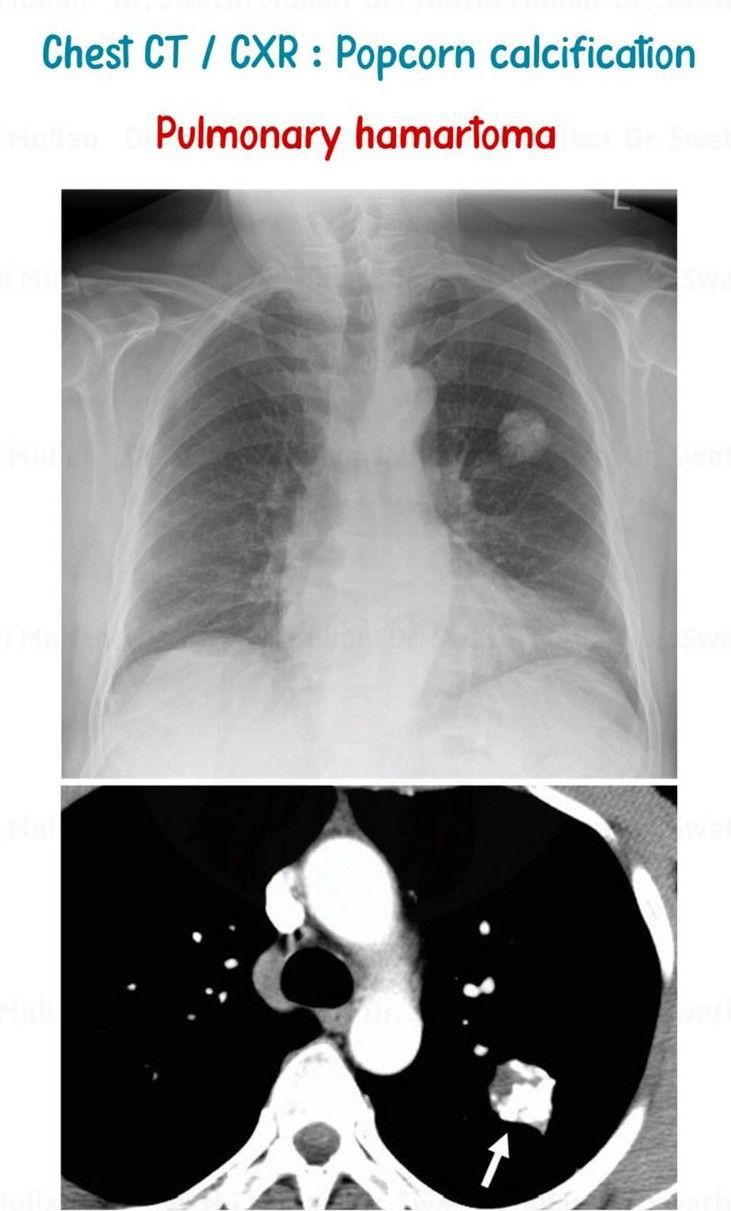

Pulmonary hamartomas are benign malformations of the lung and include an abnormal mixture of tissue components such as cartilage, epithelium, fat, or muscle which are common to the lung but the organ architecture is not preserved